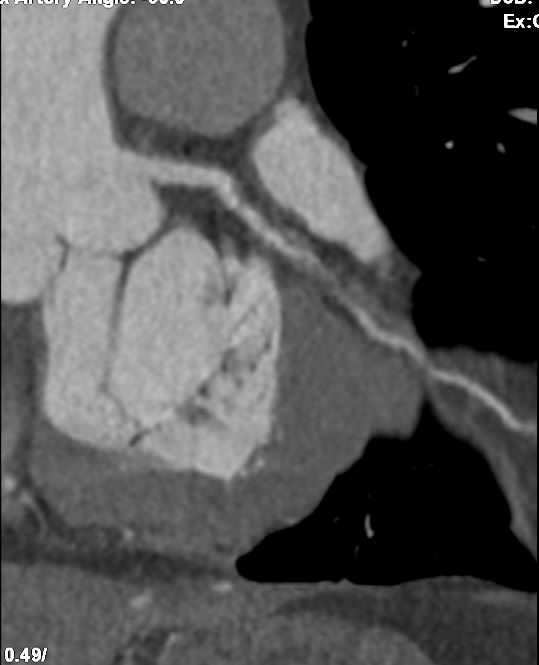

Echocardiogram showed good left ventricular ejection fraction of 53%. A multislice computed tomography coronary angiogram (MSCT-Coronary) demonstrated severe stenosis involving the proximal left anterior descending (LAD),proximal left circumflex (LCx),and proximal right coronary artery(RCA).The patient was subsequently admitted electively for diagnostic coronary angiography and possible percutaneous coronary intervention (PCI).

Angiographic assessment showed a normal left main stem, with severe proximal LAD disease exhibiting moderate calcification and providing retrograde collateral supply to both RCA and LCx. The LCx demonstrated severe mid-segment disease with subtotal occlusion of the obtuse marginal 1 (OM1) branch. The RCA showed severe proximal disease and total occlusion of the posterolateral(PL) branch.

Initial engagement with a JR3.5/6Fr guiding catheter provided suboptimal support; this was switched to a SAL 0.75/6Fr guide, which offered only modest improvement. Lesion predilatation was performed with non-compliant balloons (0.85/15 mm and 1.5/15 mm) assisted by a guide extension catheter. Intravascular ultrasound (IVUS)revealed a distal reference vessel diameter of 3.0 mm and proximal reference of 3.5 mm, with evidence of white thrombus at the mid RCA. Further lesion preparation was performed using Naviscore balloons (3.0/15 mm distally and 3.5/15 mm proximally),achieving satisfactory luminal gain. A repeat IVUS run confirmed resolution of the white thrombus. Based on this, a drug-coated balloon(DCB)-only strategy was chosen. EssentialPro DCBs (2.0/40 mm for distal-mid segment, and 3.5/40 mm for mid-proximal segment) were successfully delivered and deployed. Post-procedure IVUS demonstrated significant improvement in minimum lumen area (MLA)—from 2.91 mm©÷to 4.07 mm©÷ (distal) and 1.60mm©÷ to 6.93 mm©÷ (proximal).